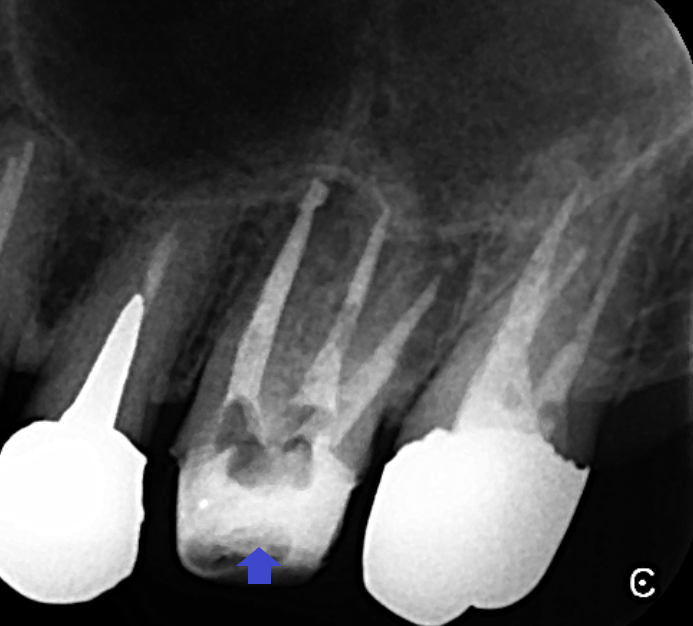

矢印の先が上顎第一大臼歯です。精密根管治療により膿の改善をはかりました。石灰化を顕微鏡下で除去し、根管充填しました。画像は、根管充填のレントゲン画像です。